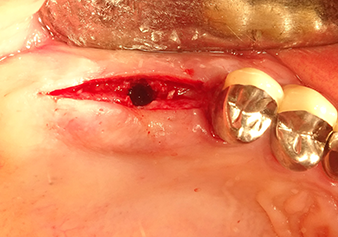

A 49-year-old female patient, a non-smoker and with nothing remarkable in her general medical history, was referred to our oral surgery practice for surgical extraction of tooth 16 and subsequent implantation. After the extraction, the patient experienced mild sinusitis trouble with the resultthat we initially waited six months before carrying out the measure. The residual bone height at the planned implant position measured 3-4 mm (Fig. 1 and 2).

Preoperative findings: The alveolar ridge has healed well, including sufficiently broad, keratinised gingiva

Fig.1: Preoperative findings: The alveolar ridge has healed well, including sufficiently broad, keratinised gingiva.